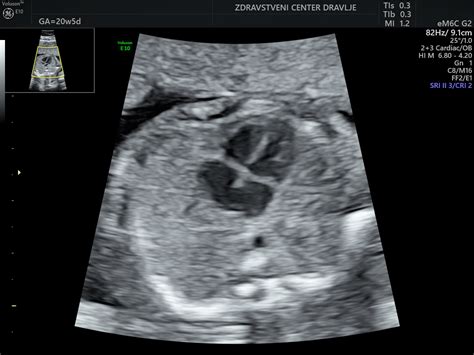

Prvi ultrazvok nosečnosti je ključen mejnik, ki običajno poteka med 7. in 10. tednom nosečnosti, čeprav se lahko pri ženskah, ki so zanosile po postopkih asistirane reprodukcije (OBMP), izvede že med 7. in 8. tednom. Namen prvega ultrazvoka je potrditi nosečnost, preveriti njeno vitalnost ter izključiti morebitno izvenmaternično nosečnost.

V zgodnji nosečnosti, zlasti v 4. in 5. tednu, je prikaz nosečnosti na ultrazvoku odvisen od več dejavnikov, vključno z dolžino menstrualnega ciklusa nosečnice in časom ovulacije. Pri ženskah z daljšimi cikli, kot je omenjeno v primeru zadnje menstruacije 11.11.2020 in ciklov med 35-40 dnevi, je nosečnost lahko bistveno krajša od pričakovane glede na zadnjo menstruacijo. V takšnih primerih se nosečnost v maternici še morda ne vidi ali je vidna le zelo majhna gestacijska vrečka.

Gestacijska vrečka, ki se prvič pojavi okoli 4. tedna gestacijske starosti, je na ultrazvoku vidna kot ehogeni obroč, ki obdaja bistro središče. Njena velikost narašča s približno 1 mm na dan do 9. tedna. Proti koncu 5. tedna nosečnosti je gestacijska vrečka običajno že zaznavna z vaginalnim ultrazvokom. V primeru, da se vidijo večje ali več "krogi podobni gestacijski vrečki", to lahko vzbuja dvom, vendar je ob ustrezni interpretaciji in ob upoštevanju individualnih značilnosti nosečnice vse mogoče.

Rumenjak, ki oskrbuje zarodek s hranili do razvoja posteljice, postane viden v 5. tednu nosečnosti in zraste do največ 6 mm. S transvaginalnim ultrazvokom se lahko srčna aktivnost ploda zazna že pred celotno maso plodovih celic, kar je potrditev vitalnosti nosečnosti. Če je merjenje dolžine plodovega odmeva (CRL - Crown-Rump Length) izvedeno, se lahko z visoko natančnostjo določi gestacijsko starost. Vendar pa v prvih tednih nosečnosti lahko zaradi zgodnejše ali poznejše oploditve ali ugnezditve zarodka, odstopanja prikažejo zelo različne slike.

Ultrazvočni pregled z vaginalno sondo potrdi vitalno nosečnost v maternici, določi število plodov in oceni velikost ploda z merjenjem razdalje teme-trtica (CRL). Ta meritev omogoča preverjanje točnosti predvidenega datuma poroda (PDP), določenega glede na zadnjo menstruacijo. Če je odstopanje večje od 7 dni, se PDP prestavi glede na ultrazvočno meritev.